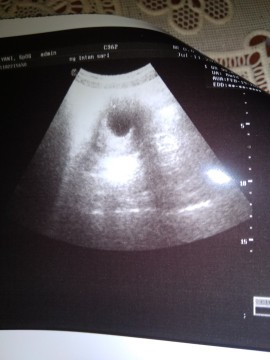

Assalamu'alaikum bunda2. Mf mau tanya usia kandungan saya 7w3d apa normal USG blm keliatan janin nya baru keliatan kantung nya aja? Bunda2 usia kandungan brpa udh keliatan janin nya?

Saya 7bwekk jg masih kantung bun... Kembali usg pas 11 wekk dedek nya udah ada dan detak jantung nya...